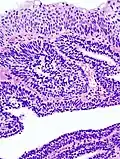

| Micrograph of an inverted papilloma of the urinary bladder; H&E stained | |

An inverted papilloma, also known as Ringertz tumor,[1] is a type of tumor in which surface epithelial cells grow downward into the underlying supportive tissue. It may occur in the nose and/or sinuses or in the urinary tract (bladder, renal pelvis, ureter, urethra). When it occurs in the nose or sinuses, it may cause symptoms similar to those caused by sinusitis, such as nasal congestion. When it occurs in the urinary tract, it may cause blood in the urine.